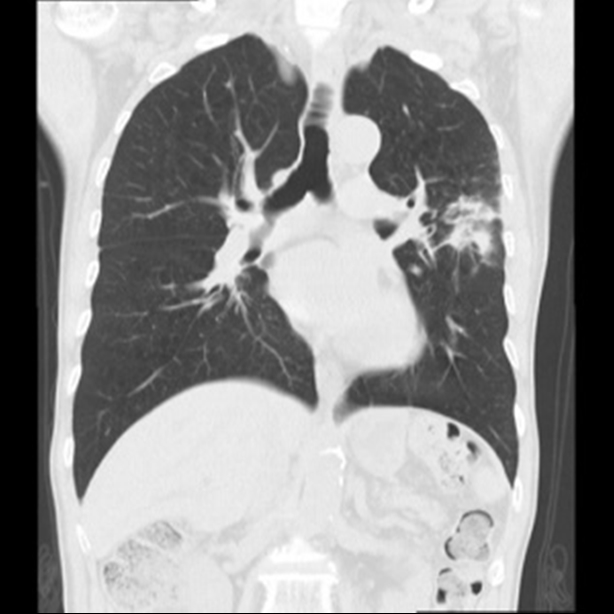

胸部CT

肺や気管、気管支などの胸部病変、胸部X線写真では見つけることが難しい小さな病変、肺炎や肺癌などの病気を見つけることができます。